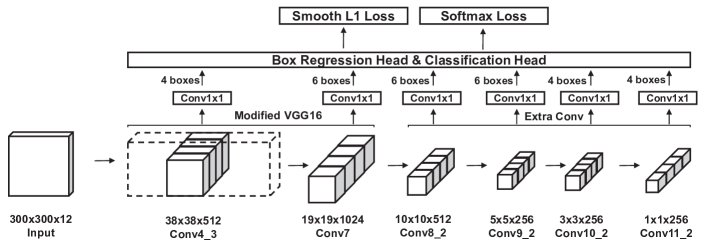

SSD is a one-stage model, which enables object detection at any scale by utilizing multi-scale convolutional feature maps (Figure 2). SSD can use any arbitrary convolutional neural networks (CNNs) as base networks. The model attaches bounding box regression and object classification heads to several feature maps of the base networks. We use the modified VGG16 [11] architecture as in the original model implementation to ensure a practical computational cost for training and inference. The loss term is a sum of the confidence loss from the classification head and the localization loss from the box regression head:

3.0.1 Grouped Convolutions

Our custom liver lesions detection dataset consists of four phases, each of them having three continuous slices of image per data point, which corresponds to 12 “channels” for each input. We could apply the model naively by increasing the input channel of the first convolutional layer to 12. However, this renders the optimization of the model ill-posed, since the convolution filters need to learn a generalized feature representation from separate data distributions. This also runs the risk of exploiting a specific phase of the input, and not fully utilizing the rich information from the multi-phase input. Naive application of the model causes severe overfitting, which means the model fails to generalize to the unobserved validation dataset.

To this end, we designed the model to incorporate grouped convolutions. For each convolutional layer of the base networks, we applied convolution with separate filters for each phase by splitting the original filters, and concatenated the outputs to construct the feature map. Before sending the feature map to the heads, we applied additional 1x1 convolutions. This induces parts of the model to have separate roles, where the base networks learn to produce the best feature representation for each phase of the input, while the 1x1 convolutions act as a channel selector by fusing the grouped feature map [24, 23] for robust detection.